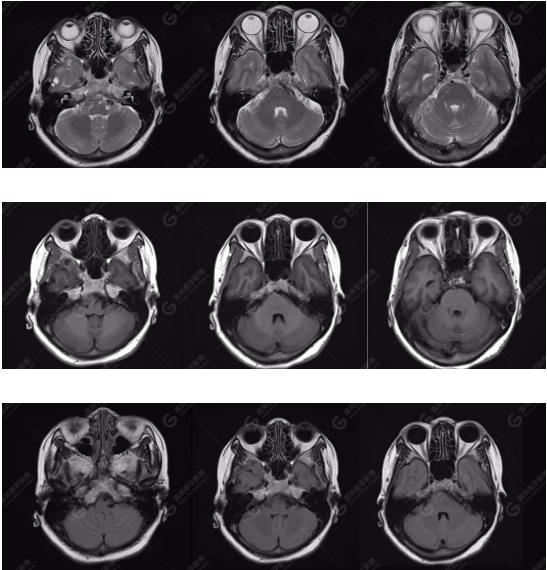

MRI平掃所見

雙側(cè)大腦半球?qū)ΨQ,灰白質(zhì)對比正常,右側(cè)顳部見一囊狀長T1長T2信號影,F(xiàn)LAIR序列呈低信號;余腦實質(zhì)內(nèi)未見局灶性信號異常。各腦室、腦池大小、形態(tài)均正常,中線結(jié)構(gòu)居中,幕下小腦、腦干無異常。矢狀面示垂體大小形態(tài)正常,未見局灶性信號異常。

顱腦MRA及ciss序列示腦基底動脈環(huán)完整,雙側(cè)頸內(nèi)動脈末段、大腦前動脈、大腦中動脈、大腦后動脈及其主要分支顯影良好,管徑及走行正常,無明顯局灶性增粗或變細(xì)。雙側(cè)椎動脈末段沿延髓左側(cè)向上走行,左側(cè)面聽神經(jīng)輕度受壓移位,左側(cè)面聽神經(jīng)周圍見細(xì)小血管包繞。右側(cè)面聽神經(jīng)及雙側(cè)三叉神經(jīng)周圍未見異常血管影。